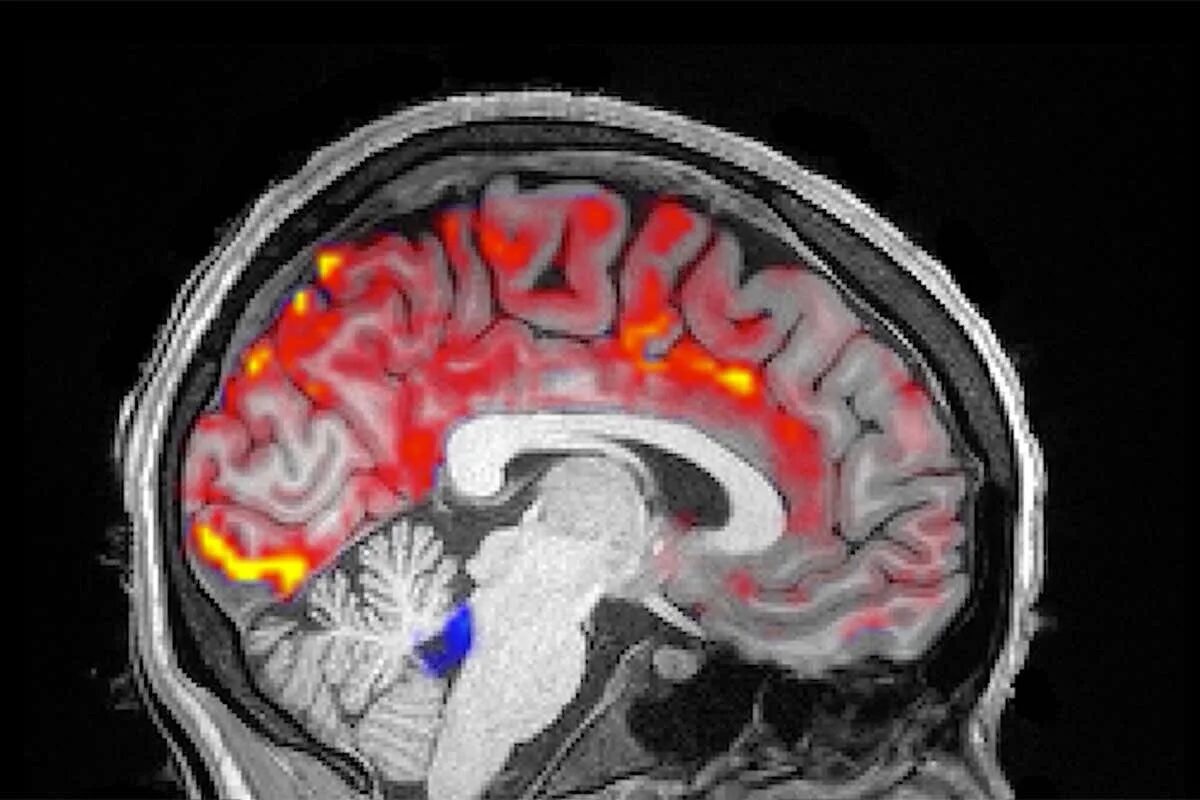

Sleeping brains